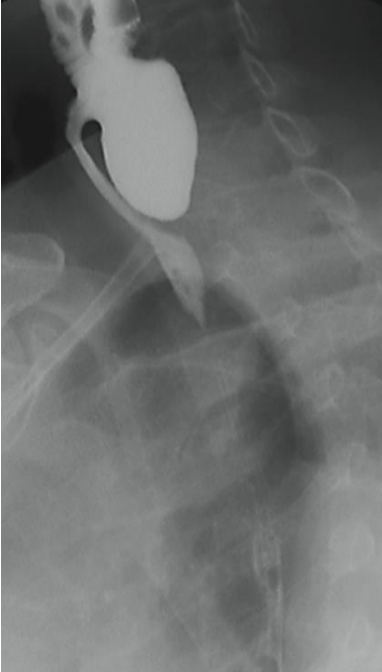

Imagem de um esofagograma em incidência lateral oblíqua evidencia a seguinte imagem, que corresponde a: